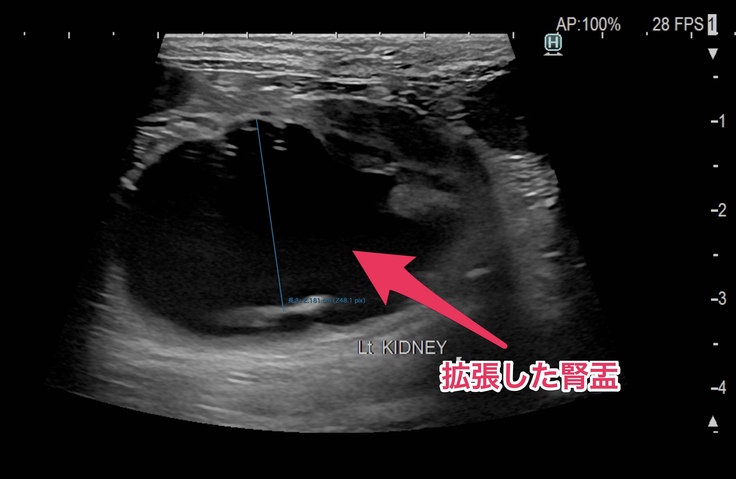

📣1つ目は何かしらの原因で尿管が詰まっていて左側の腎臓と腎盂が肥大して左側の腎臓がほぼ機能していない状態。

🐈CT検査とエコー検査でも左側の腎臓と腎盂の肥大、尿管のどこかが詰まっているためにおしっこが流れていかずに拡張した尿管が確認されました🐈

🐈左の腎盂。黒い影がぱんぱんに膨らんでいます🐈

今は右側の腎臓と腎盂機能が正常で、機能していない左側の腎臓の分までカバーしてくれているので血液検査でも異常な数値は出なかったけど、右の方も左側と同じように詰まってしまえば腎臓の機能がストップしてしまうので尿毒症や腎不全になったりして食欲不振や嘔吐するようになって体調が良くない日が多くなったり、透析等の別の治療が必要になる場合もあるかなと説明を受けました。